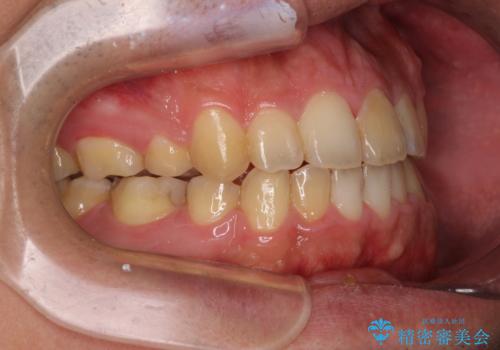

後戻りでデコボコの前歯 インビザライン矯正治療

- 高校時代に行った抜歯矯正が後戻りをしたとのことで来院された患者様です。

再矯正であることから、目立ちにくい装置を希望されたため、インビザラインにて矯正治療を行うこととしました。

下顎骨が左側に変位しているため、正中が合わないことは予想できましたが、歯列が整った後も咬み合わせが安定せず、咬み合わせを落ち着かせるために1年以上の期間を要しました。